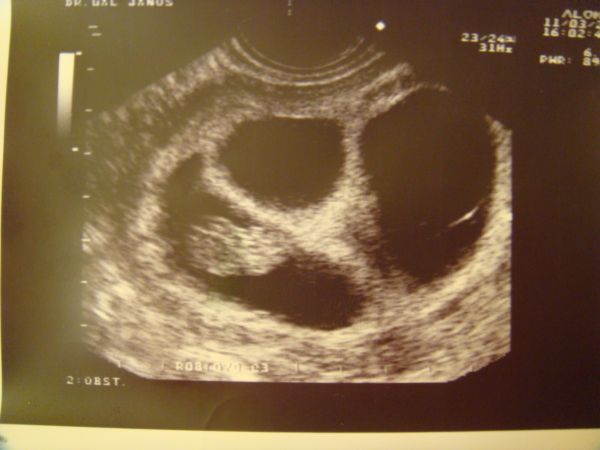

KépKép

Két babó

1 babó

Sajnos egyszerre nem férnek rá. :lol: